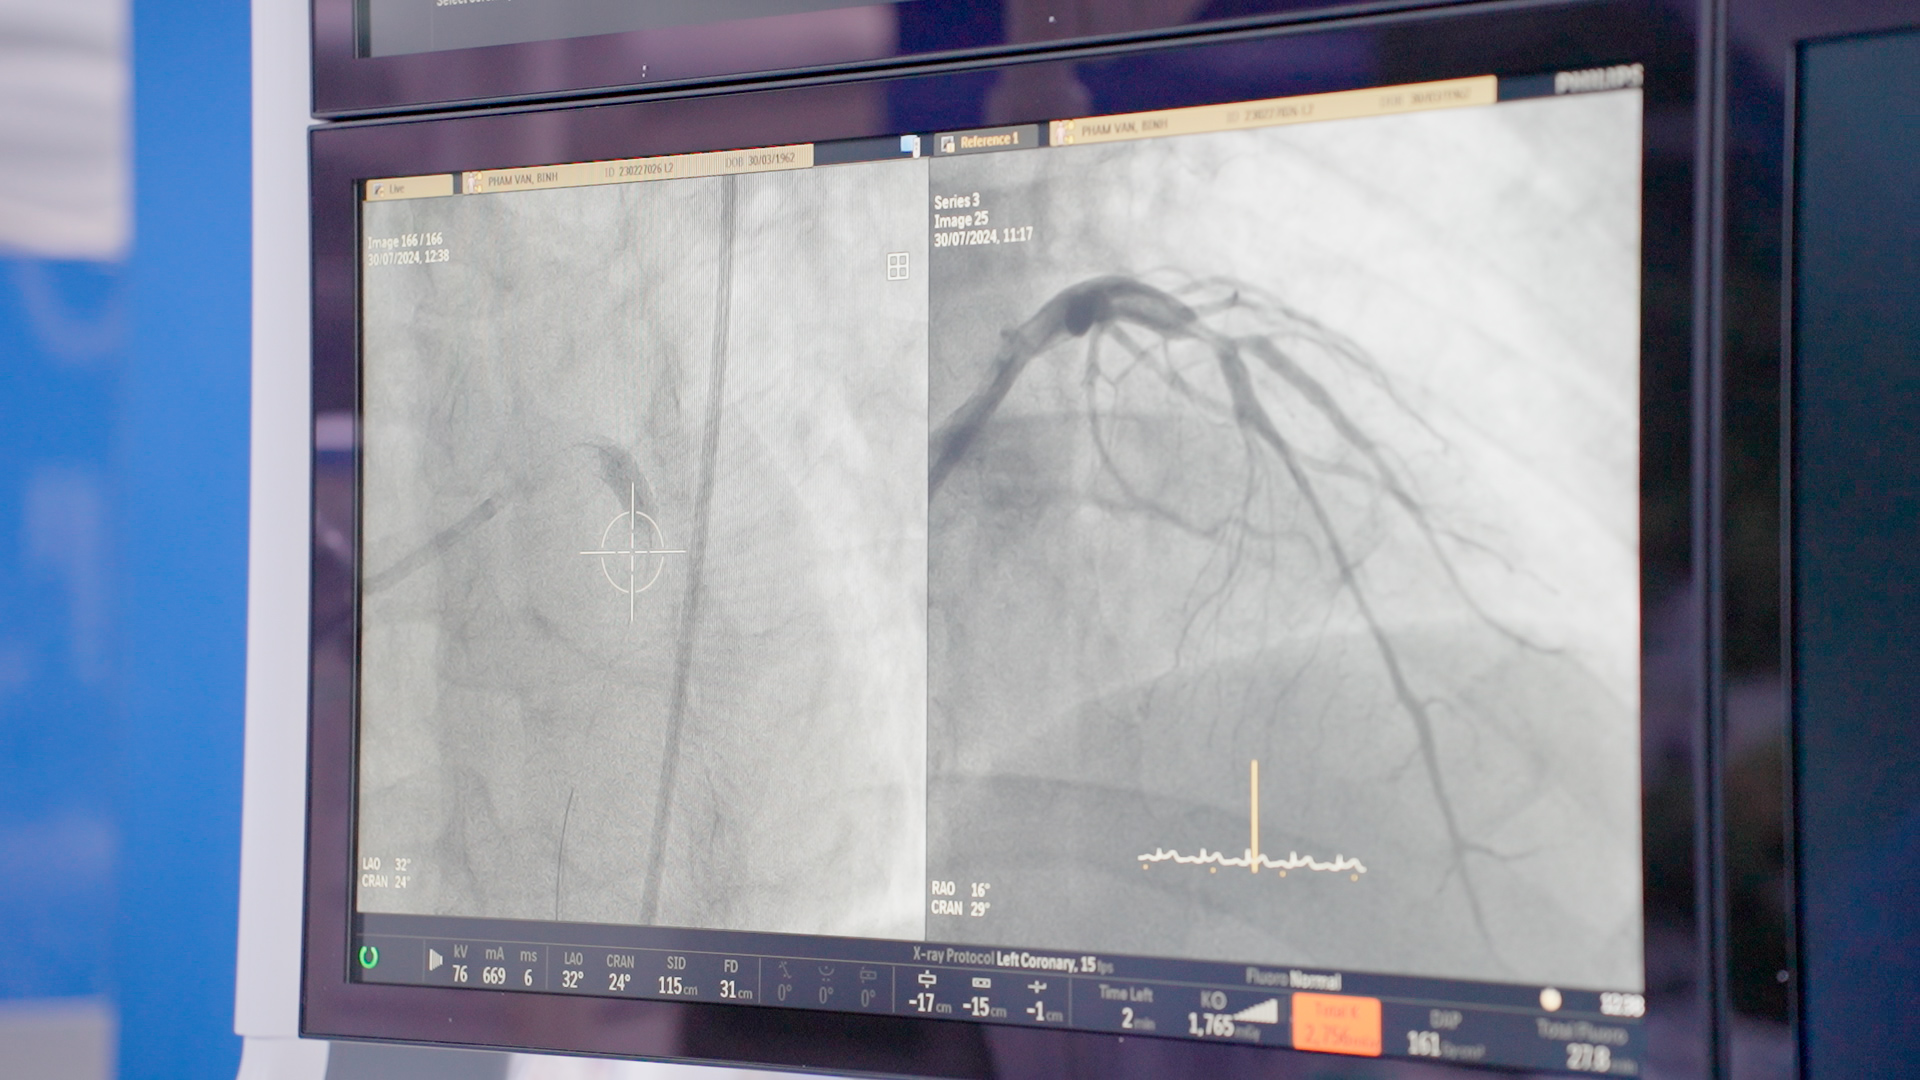

Tình trạng trước và sau khi can thiệp thành công bằng kỹ thuật nong bóng phủ thuốc cho bệnh nhân bị hẹp mạch vành nặng tại BVĐK Hồng Ngọc